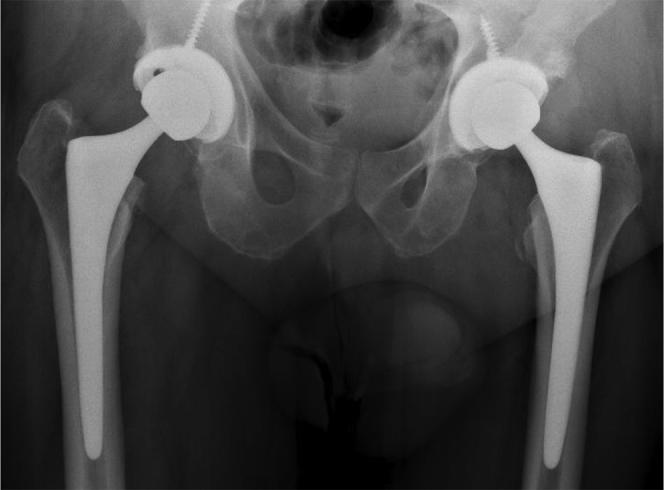

Fifteen of the 21 patients were referred from musculoskeletal providers (12 from orthopaedic surgeons). Prior to diagnosis of the hip etiology, 16 patients were reduced to major assistive devices including wheelchairs. Twelve of 21 patients had undergone surgical knee interventions, including total knee arthroplasty, with minimal to no relief of their pain. Seventeen of 21 referred patients underwent total hip arthroplasty at our institution. Fourteen patients had complete resolution of knee pain after total hip arthroplasty.

Although knee pain referred from hip disease may be considered a basic and common knowledge, it continues to be an overlooked phenomenon. Most of the cases were misdiagnosed by musculoskeletal providers including orthopaedic surgeons and this highlights the need for continued education and awareness of this clinical scenario.